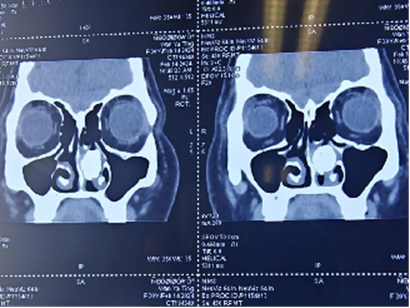

近日,西安市长安区医院耳鼻咽喉头颈外科接诊了一例长期鼻塞患者。据了解,患者万某,左侧鼻塞、流涕症状已持续长达15年。但患者并未给予足够重视,导致鼻塞症状逐渐加剧,严重影响生活质量。患者在当地医院就诊,经鼻内镜检查发现左侧鼻腔存在灰白色质硬增生物。鼻窦CT扫描结果进一步提示左侧鼻腔存在片状高密度影,考虑有骨瘤可能。为寻求进一步治疗,万某多方咨询,来到西安市长安区医院耳鼻咽喉头颈外科就诊。

鼻窦CT扫描显示左鼻腔高密度影